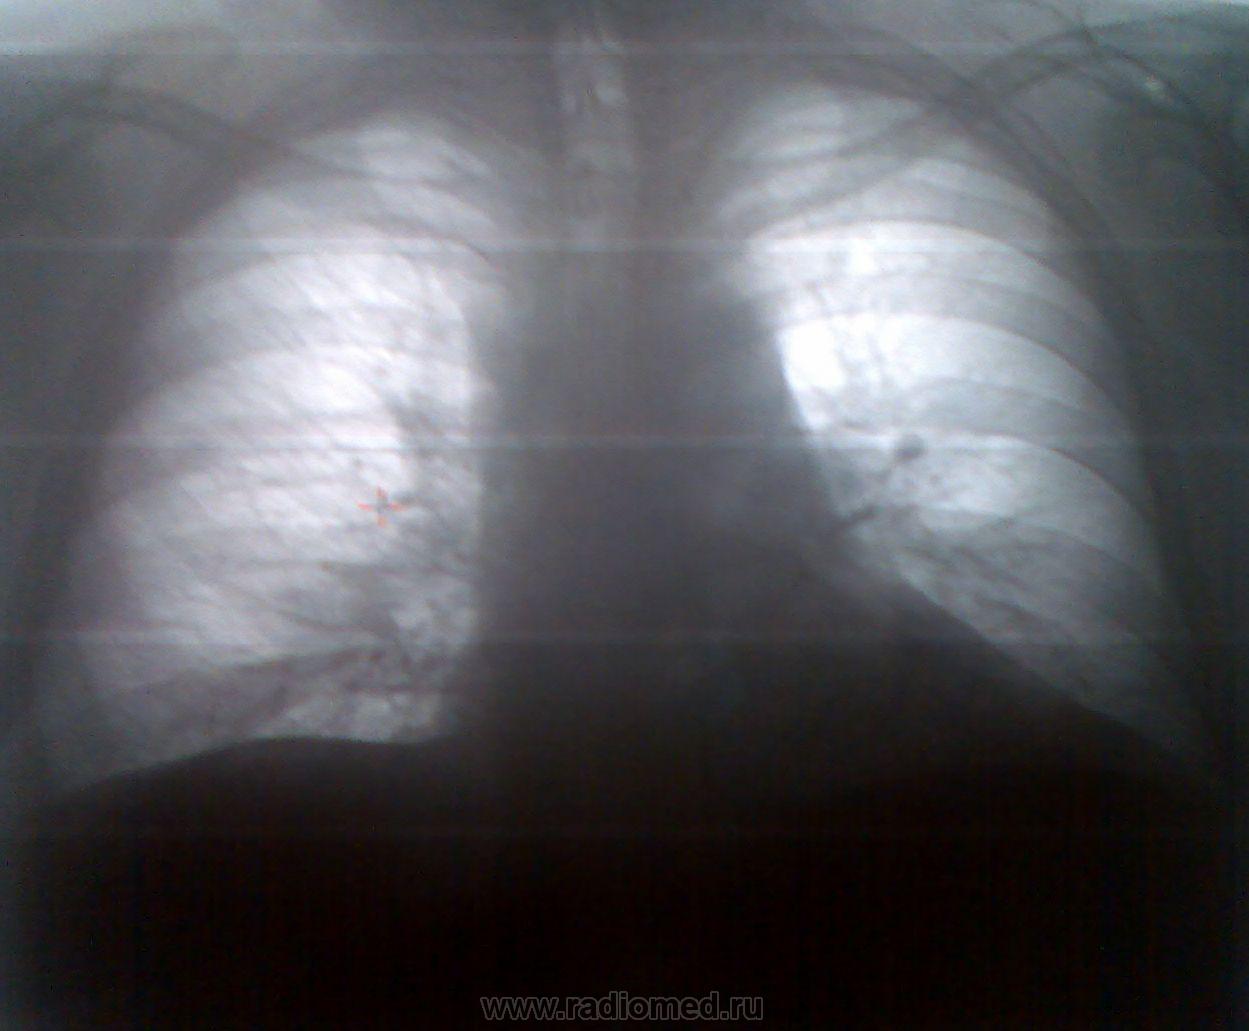

Уважаемые коллеги! В продолжение темы рентгенологической диагностики вирусных пневмоний, предлагаю следующее клиническое наблюдение. Пациент, мужчина, 37 лет. Гиперстеник, вес около 130 кг, что несколько затруднило проведение рентгенологических исследований. И цифровая ФЛГ, рентгенограммы пересняты мобильником. Ну что получилось, то и получилось. Итак, пациент поступил в пульмонологическое отделение на 2-й день заболевания с диагнозом - острая пневмония. Представляю цифровые ФЛГ.

Изображение      Изображение

По данным ФЛГ мои коллеги-рентгенологи заключили, что у пациента имеется левосторонняя, нижнедолевая(S10) сегментарная пневмония. Начата противовоспалительная терапия.

Последующие рентгенограммы выполнялись уже в отделении АиР, начиная с 3-го дня пребывания в стационаре (5-го дня от начала заболевания) каждые сутки. Комментарии опущу.

Как Вы видите, уважаемые коллеги, на серии рентгенограмм резко отрицательная динамика за короткое время. Так же и клиническая картина. За короткое время от легкого недомогания, покашливания до отека легких и сердечно-сосудистой, дыхательной недостаточности, приведшей к гибели пациента. При этом отмечу очень интенсивную терапию, проводившуюся пациенту.

И в заключении, не буду задерживать Ваше внимание. Так протекает пневмония, вызванная гриппом А(H1N1). Диагноз верифицирован посмертно. Рентгенологических патогномоничных симптомов не имеет. Практически так же выглядела рентгенологически, ранее демонстировавшаяся мною на сайте, "болезнь легионеров". Да и любая субтотальная, тотальная пневмония.